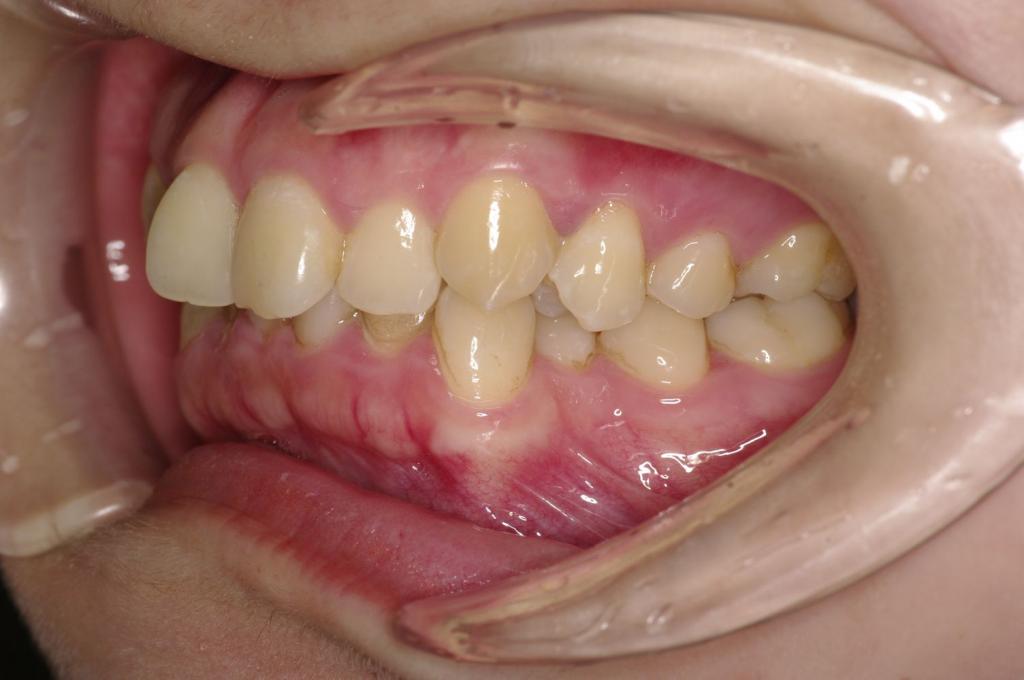

前歯、出っ歯・開咬の矯正治療

(治療期間、治療前後写真、治療方法、費用)WORKS